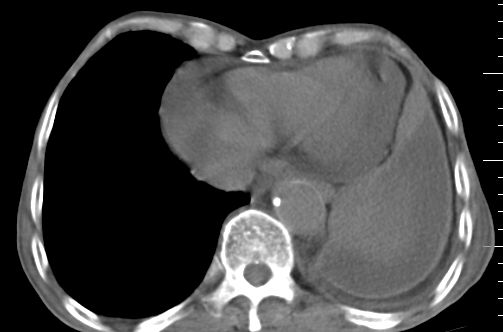

标题: CT10141:男、84岁,咳嗽、咯血1年。 [打印本页]

标题: CT10141:男、84岁,咳嗽、咯血1年。

支持左侧中央型肺癌伴下叶肺不张\\纵隔淋巴结转移.左侧包裹性胸腔积液\\心包积液.左侧少量胸腔积液..慢性支气管炎伴部分间质纤维化.

支持:左侧中央型肺癌伴下叶肺不张\\纵隔淋巴结转移.左侧包裹性胸腔积液\\心包积液.左侧少量胸腔积液..慢性支气管炎伴部分间质纤维化.另:支气管分支根部明显阻塞 狭窄,内膜凸凹不平,提示内膜增生物。

咯血病史较长,左肺下叶实变,体积未明显缩小,隐约可见血管影及坏死阴影,双肺门及纵隔淋巴结增大,心包增厚积液,纵隔右移位,单侧胸腔积液,首先考虑:大叶型肺泡癌伴纵隔心包转移。